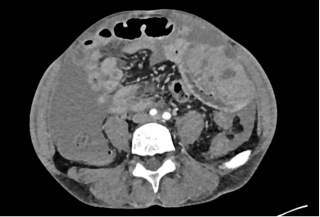

Case presentation

A 77-year-old man with a history of arterial hypertension, chronic alcohol use, gait disorders, and umbilical hernia repair, was admitted with acute left upper quadrant pain and repeated vomiting. Upon admission, vital signs where stable, but clinical exam revealed abdominal distension with peritoneal signs. An abdominal computed tomography scan (Figure 1) showed marked gastric distension, parietal pneumatosis and portal and mesenteric vein gas along with small bowel ileus, without signs of perforation. Additionally, a lesion in the right colonic’s flexure raised suspicion of a neoplasic lesion.

Initial management included nasogastric tube placement via gastroscopy. Exploratory laparoscopy revealed necrosis of the gastric greater curvature (Figure 2), confirmed by intraoperative gastroscopy, which showed transmural necrosis extending to the oesophagogastric junction. The patient’s condition deteriorated, leading to septic shock requiring significant adrenergic support. Following conversion to an open laparotomy, a total gastrectomy was performed, employing a damage control strategy that left the esophageal and duodenal stumps. After achieving hemodynamic stability, the planned second look procedure included eosophagojejunal anastomosis with Roux-en-Y reconstruction, feeding jejunostomy, cholecystectomy, and right hemicolectomy with ileo-colostomy for the suspected neoplasic lesion. Remarkably, the patient recovered without postoperative complications and was discharged to a rehabilitation program.